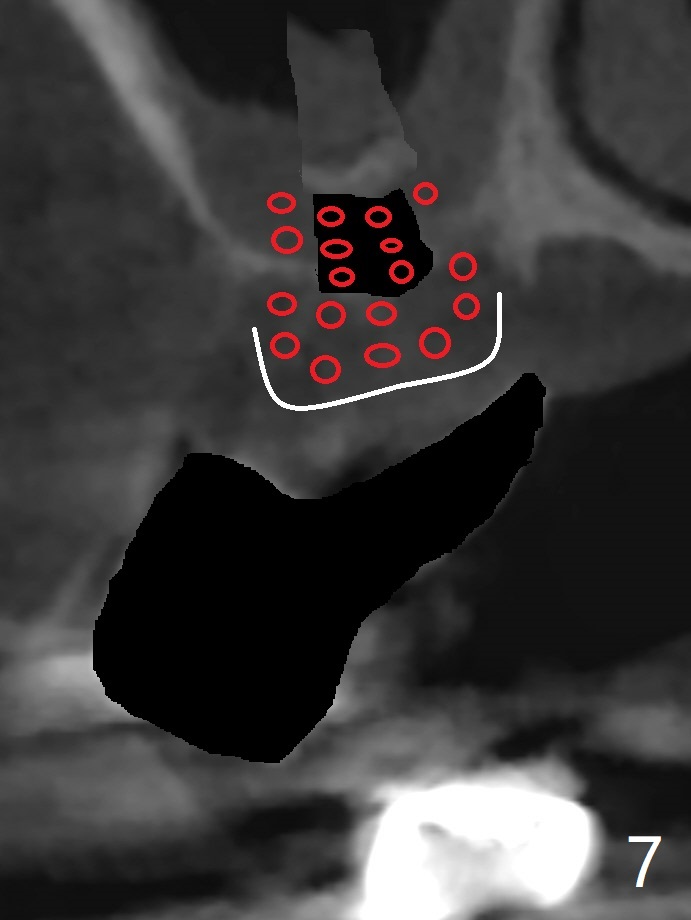

A 51-year-old woman has poor dentition with chronic periodontitis (Fig.1). She has financial constraint, but refuses RPD, insisting upon UR posterior implants first. After discussion of severe bone loss, she agrees with bone graft first (Fig.2-4). Since the bone atrophy is the most severe at #3 (Fig.5 coronal section; L: lingual), sinus lift (Fig.6 arrow) is conducted after extraction (black). Use sticky bone (Fig.7 red circles) and Titanium-reinforced Cytoplast (white) for socket preservation. Or if Magicore is able to achieve primary stability (Fig.8 green), an abutment (pink) will be placed for an immediate provisional (white). The latter are capable of holding bone graft in place. Since bone loss at #2 and 4 is less severe (Fig.9 sagittal section), their roots will act as walls to keep bone graft (Fig.11) in place after #3 extraction (Fig.10).